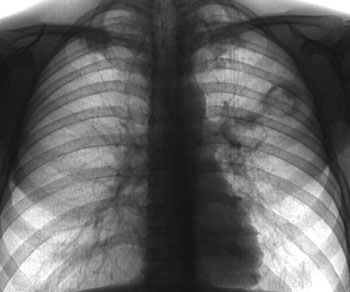

Это вид туберкулеза, проявляющийся острым воспалением легкого. Развитие заболевания происходит при повторном инфицировании заживающих участков легкого.